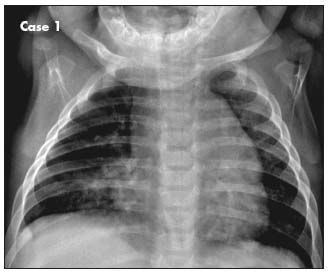

This chest radiograph shows a normal heart contour with an upper border merging with thymic tissue, a right middle lobe infiltrate, and peribronchial cuffing in both lung fields. The infant's intermittent wheezing, stable cardiac lesions, and acute pulmonary infiltrate favor a diagnosis of recurrent respiratory illness, manifested as acute bronchiolitis and right middle lobe pneumonia.

Image courtesy Linh Thi My Ha, MD and Golder N. Wilson, MD, PhD.